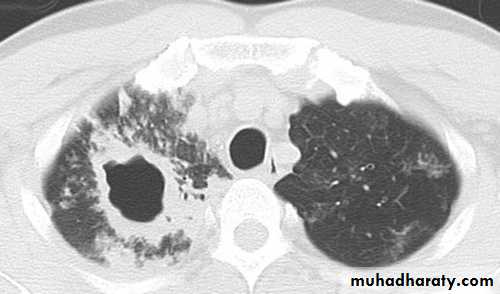

(a) Chest x-ray and (b) CT scan from a 27-year-old student with disseminated tuberculosis . Multiple small opacities (miliary shadowing) are seen in the periphery of the chest x-ray and much more clearly in all areas of the CT scan